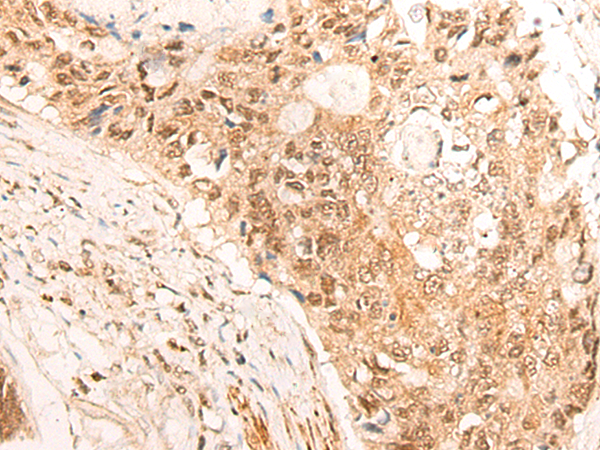

分类: 科研抗体货号: P13261别名: DSC; DSC1; DSC2; DSC4; CDHF3; HT-CP应用: IHC反应种属: Human, Mouse